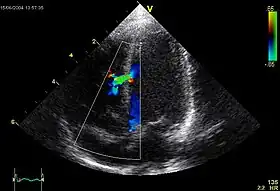

![]() An abnormal echocardiogram: Image shows a midmuscular ventricular septal defect. The trace in the lower left shows the cardiac cycle and the red mark the time in the cardiac cycle when the image was captured. Colors are used to represent the velocity and direction of blood flow. | |